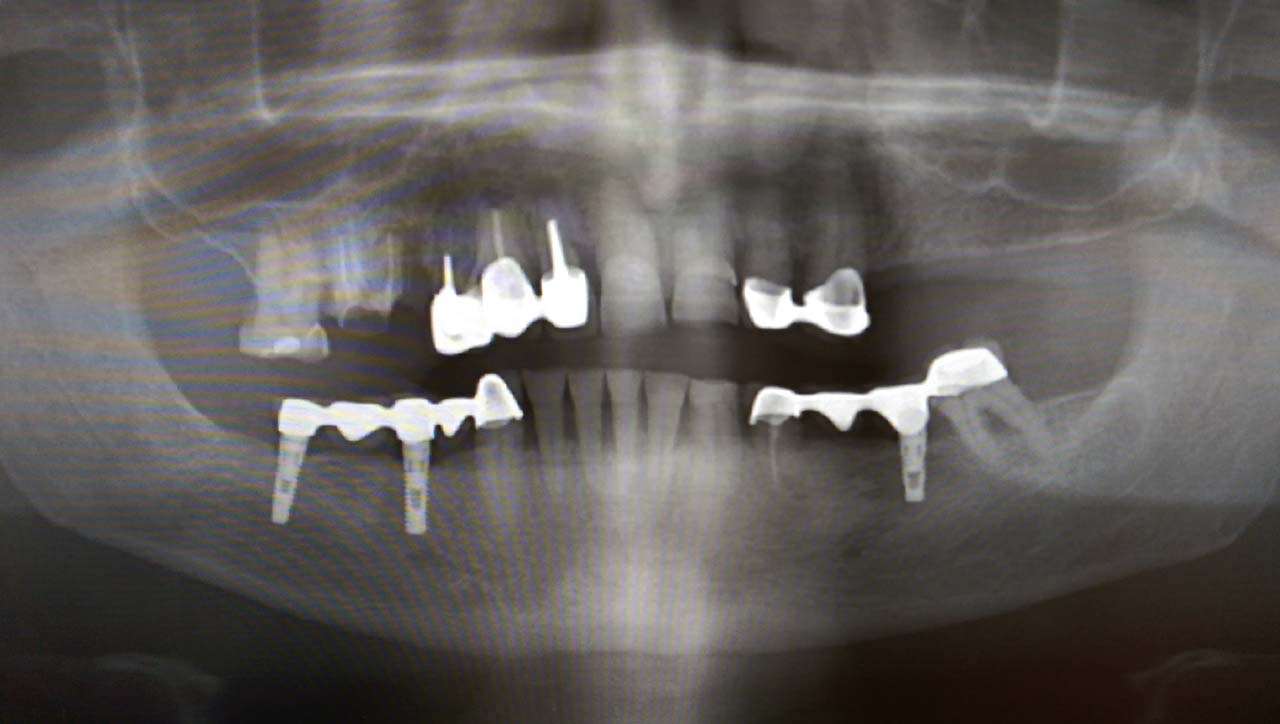

Alsó állcsont teljes rehabilitációja 72 óra alatt, azonnal terhelhető implantátumokkal súlyos paradontitisben szenvedő dohányzó páciens esetében. Az alsó állcsont fogai mind mozogtak az előrehaladott fogágypusztulás miatt.

A fogakat eltávolítottuk, a gyulladt, fertőzött csontot kitakarítottuk, kifertőtlenítettük, majd azonnal implantáltunk.

Svájci, IHDE márkájú, azonnal terhelhető implantátumokat helyzetünk be, és ezekre harmadnapra rögzített, hosszútávú, fémvázas, esztétikus műanyaggal leplezett hidat ragasztottunk be.

Ezt az ideiglenes hidat a sebek gyógyulása miatt használjuk, de tartóssága miatt véglegesként is használható.

A legtöbb esetben, ahogy itt is, 6 hónap múlva porcelán hídra cseréljük, a teljes gyógyulás után.